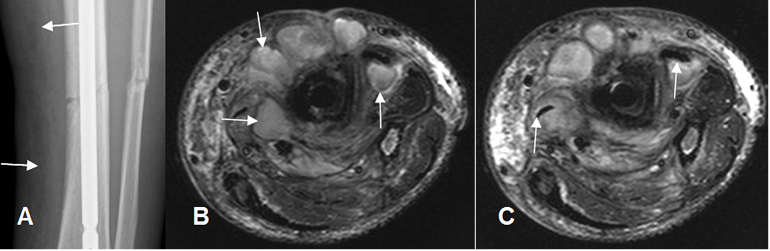

Fig 45 B. Osteomielitis crónica.

A: Rx AP. PostQx de fracturas expuestas en la pierna y clínicamente cambios inflamatorios en la extremidad. Hay fractura parcialmente consolidada de la tibia, fijada con clavo endomedular. Prominencia de los tejidos blandos e imágenes radiolúcidas que hacen sospechar la presencia de aire.

B y C: RM axial en T2. Cambios inflamatorios en los tejidos blandos, con múltiples colecciones que rodean el foco de fractura. Dentro de la colecciones en C, hay imágenes alargadas e hipointensas, que corresponden a burbujas de aire.